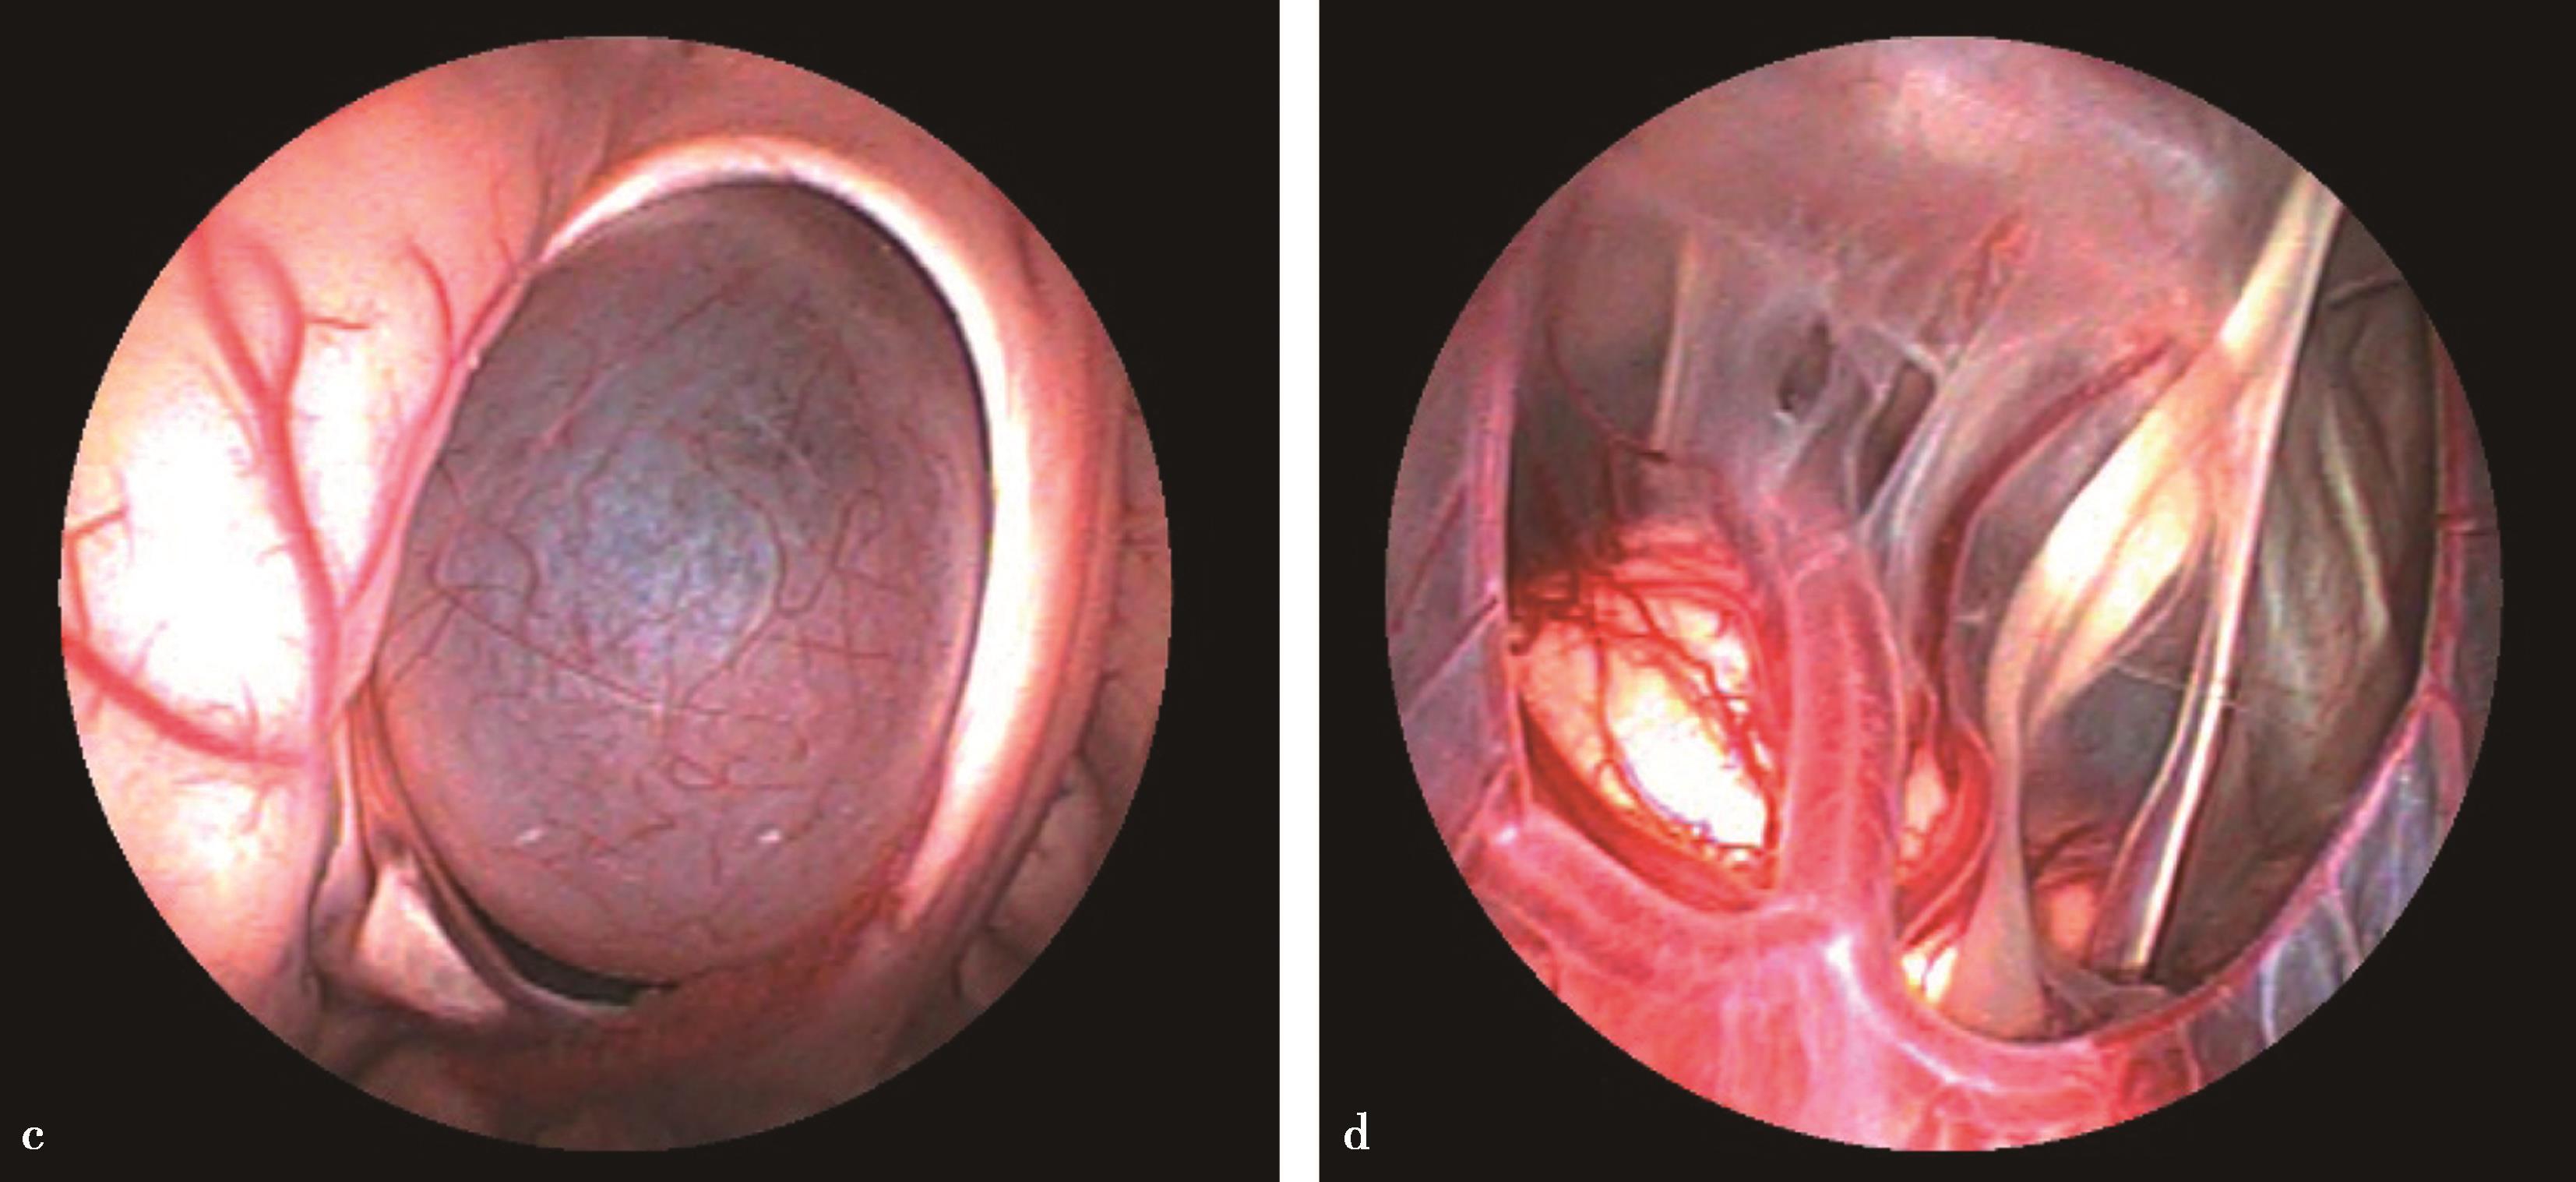

图3-1-1-4 感染后脑积水内镜下探查所见

a.脑室壁上的菌斑;b.脑室内结核所致干酪样坏死物;c.脑室内真菌感染;d.第四脑室内囊虫